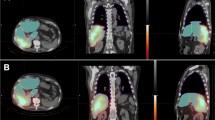

In 24 patients (57.1%), 90Y-microspheres were administered in the same location as 99mTc-MAA in the planning angiography and showed great accuracy in distribution (Fig. 2). In 18 patients (42.9%), 90Y-microspheres were injected differently, either more selectively or only to one lobe for a sequential treatment approach. For glass microspheres (n = 8), we observed a non-significant upward trend in tumor absorbed dose with 203.21 ± 105.78 (range: 0.68–344.44) Gy calculated from 90Y PET/CT vs. 155.11 ± 107.83 (range: 11.91–353.10) Gy from 99mTc-MAA SPECT/CT (P = 0.35). This trend was not seen in normal tissue absorbed dose which stayed consistent with 39.23 ± 27.62 (range: 12.28–80.68) Gy from 99mTc-MAA SPECT/CT vs. 30.50 ± 27.95 (range: 5.67–74.43) Gy calculated from 90Y PET/CT (P = 0.57). Figure 3 shows a patient treated with glass microspheres with a sequential treatment approach and selective treatment of liver segment 1. For resin microspheres (n = 10), different catheter position did not make a change in absorbed doses: For tumor, 62.32 ± 44.59 (range: 0.71–160.78) Gy calculated from 99mTc-MAA SPECT/CT vs. 61.97 ± 32.22 (range: 20.75–130.03) Gy from 90Y PET/CT (P = 0.98); and for normal liver tissue, 22.26 ± 10.83 (range: 3.46–33.75) Gy vs. 33.48 ± 17.03 (range: 8.83–57.61) Gy (P = 0.14), respectively. Data are shown in Table 3.

Sity-five-year-old male patient with a large HCC in segment 8/7 measuring 10.4 × 8.8 × 7.5 cm. He was treated with glass microspheres in a palliative attempt to control the growth of disease and cause hypertrophy in the left lobe in preparation for surgery. a Pre-treatment planning with SPECT/CT (A1, MIP; A2-A3, axial fused SPECT/CT, and CT, respectively) after intraarterial delivery of 111 MBq 99mTc-MAA via the right and 48 MBq via the left hepatic artery. Hepato-pulmonary shunt was 3%. Post-treatment SiPM PET/CT (B1, MIP; B2-B3, axial fused PET/CT, and CT, respectively) obtained after selective administration of 0.81 GBq 90Y-glass microspheres via the segment 7, 2.73 GBq via the segment 5/8 trunk and 0.95 GBq via the segment 4 artery. 90Y PET/CT shows selective distribution of microspheres in the tumor. b Dose-volume histogram of simulation 99mTc-MAA SPECT/CT and 90Y PET/CT